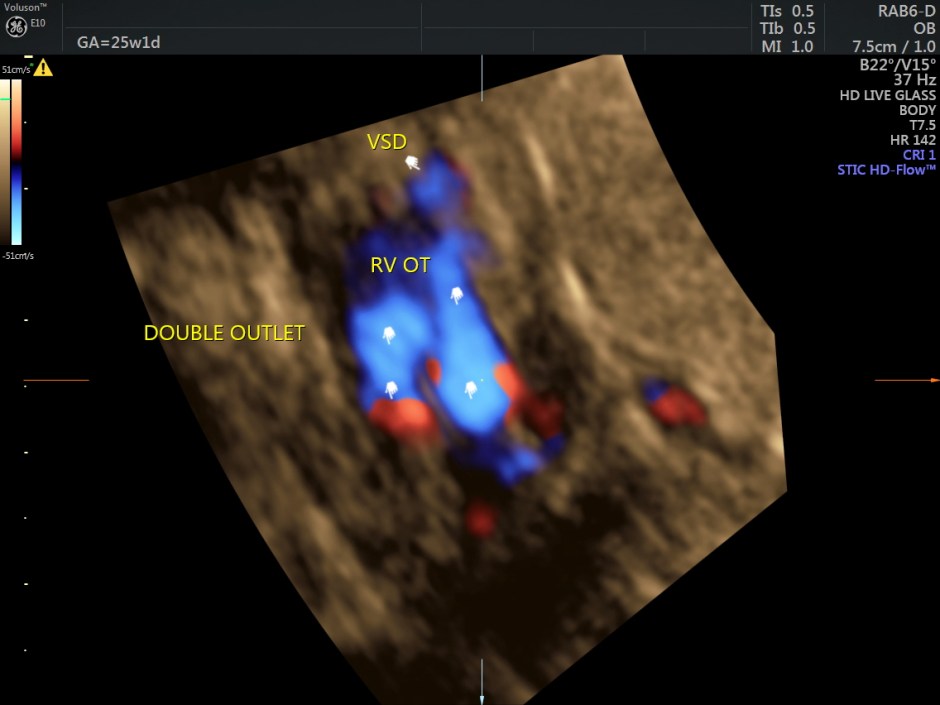

The following are some reconstructions.

This fetus showed left heart dysplasia, a small VSD and Double Outlet Right Ventricle with malposition of the great arteries.